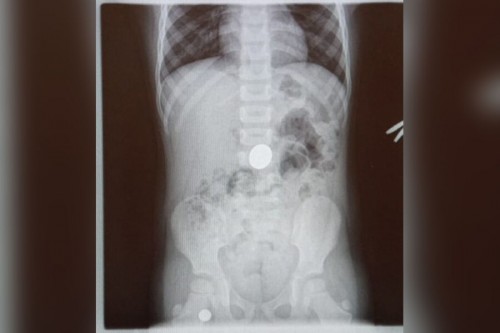

09.04.2026В дежурную часть МО МВД России «Бузулукский» поступило сообщение о госпитализации двухлетней девочки с инородным телом в желудке.

Предварительно сотрудниками полиции установлено, что девочка проглотила монету, находясь в гостях у бабушки.

Ребенок был госпитализирован, монета успешно извлечена эндоскопическим путем. В настоящее время состояние ребенка удовлетворительное, угрозы жизни нет. По факту произошедшего проводится проверка.